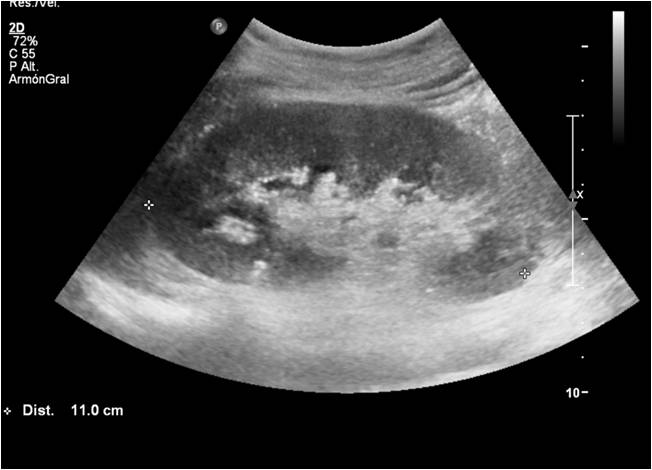

Ecografía riñón izquierdo

Ecografía riñón derecho